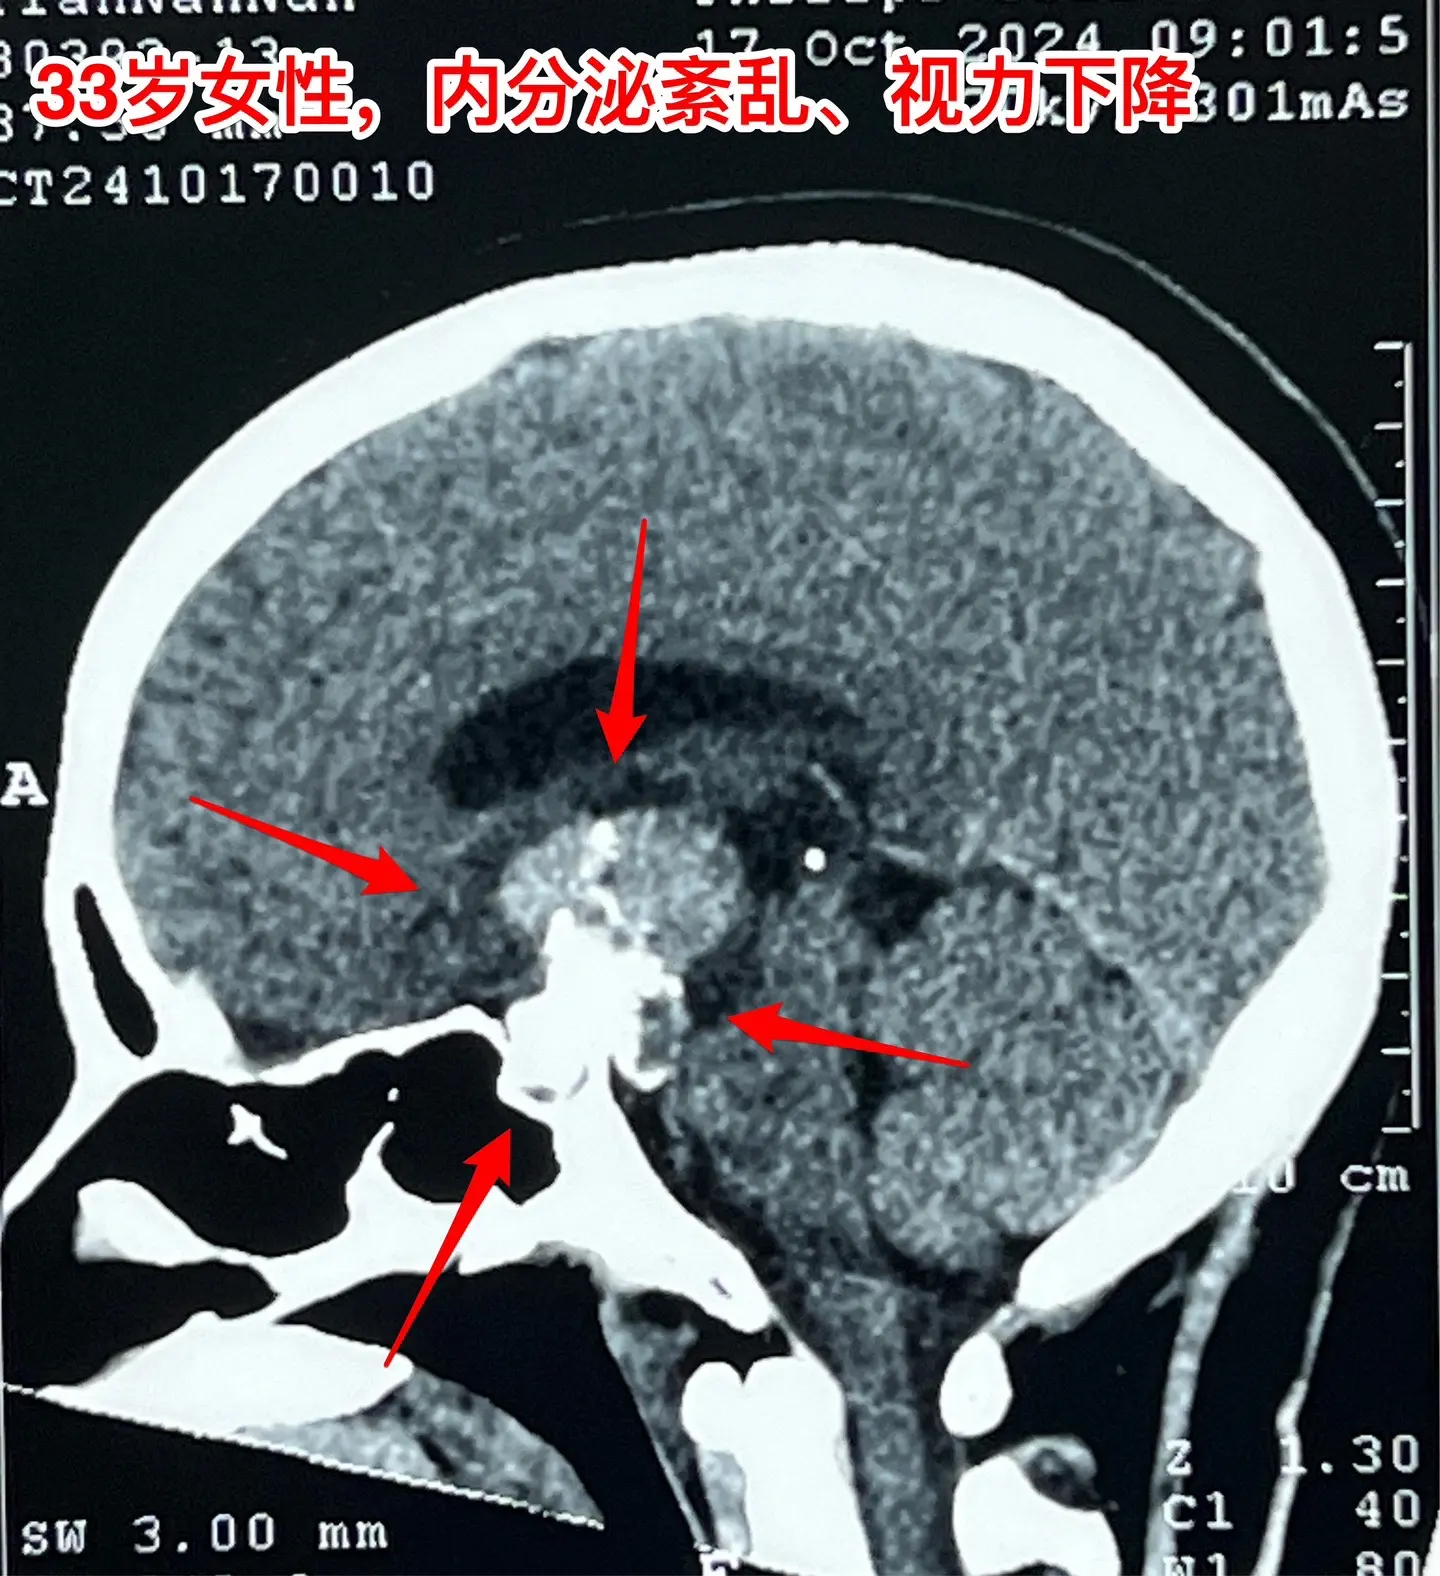

33岁颅咽管瘤患者终于下决心作手术了。洛阳市的女教师,2021年因内分泌紊乱到医院检查,就发现了颅咽管瘤。 由于对手术感到恐惧,再加上工作原因和其他原因,患者一直在观察中,未作手术。 她认识好几个曾经在我这里作过手术的颅咽管瘤病友,每一个成功的手术对她都是一次鼓励! 今年八月份患者和我联系了,说磁共振显示肿瘤在增大,有脑积水了,她也有多睡症状,视力有下降。所以她下定决心要来作手术。 10.28行开颅手术将肿瘤完全切除。肿瘤内有大块钙化,将肿瘤完全切除。手术后患者自述视力有好转。